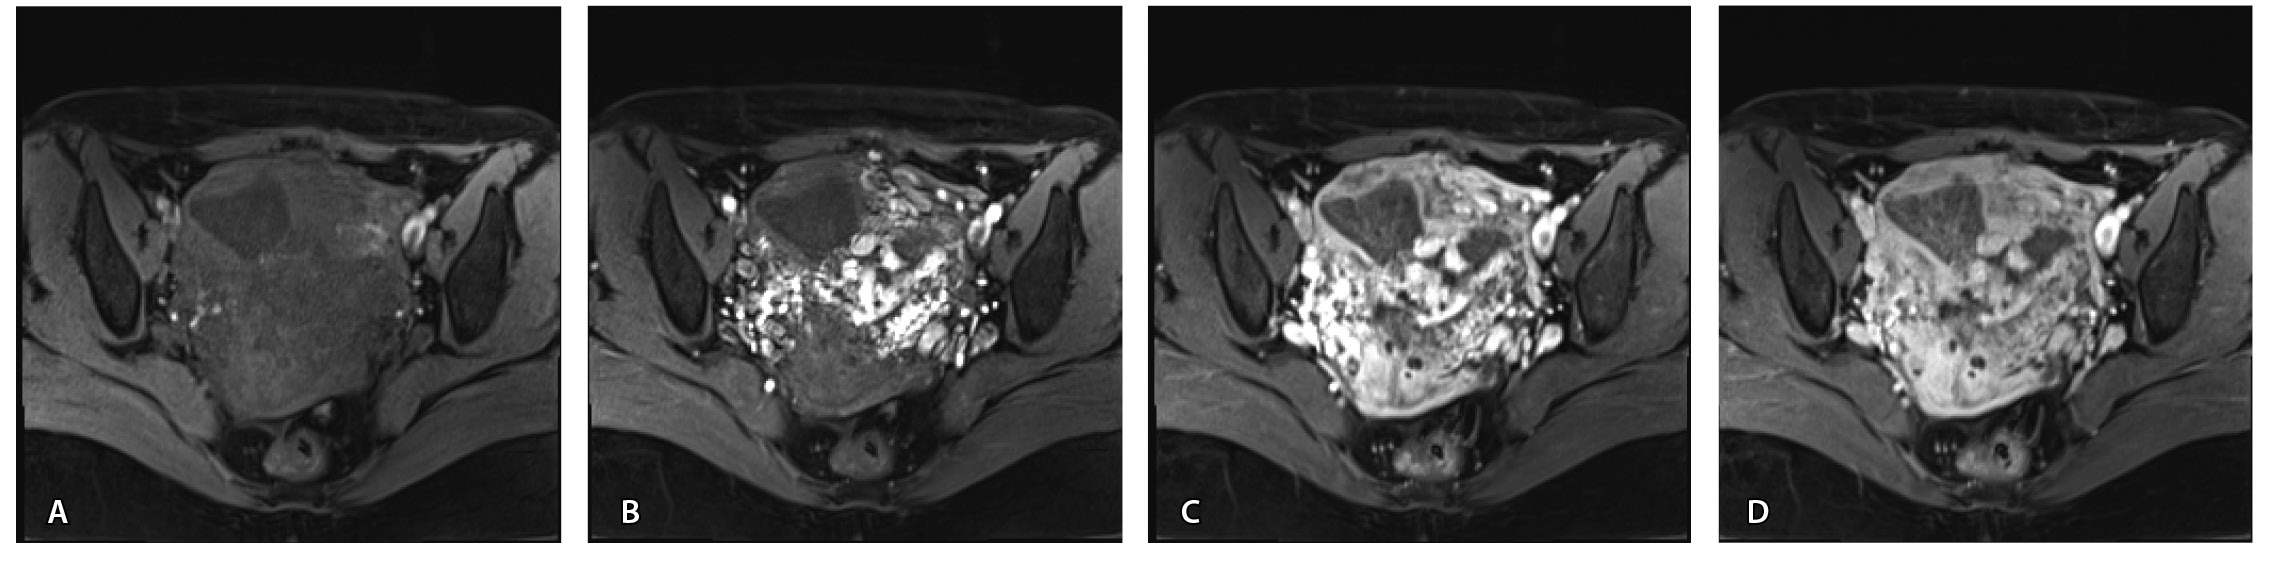

Пациентке выполнено МРТ-исследование на МР-томографе Siemens MAGNETOM Verio с индукцией магнитного поля 3T, с использованием стандартных катушек, в режимах Т1-взвешенного изображения (ВИ), Т2-ВИ, Т2-FS, FIESTA, DWI с получением изображений в сагиттальной, корональной и аксиальной плоскостях, динамическое внутривенное контрастирование (гадопентетовая кислота 0,2 мл/кг массы тела). Матка увеличена в размерах, с признаками снижения зональной дифференциации стенок, усиленным сосудистым компонентом, полость матки расширена с наличием примеси геморрагического содержимого, неравномерным утолщением эндометрия и пристеночными компонентами слизистой. В нижнем маточном сегменте определяется несостоятельный рубец от кесарева сечения, с наличием участка резко истонченной пролабирующей стенки матки слева и наличием дополнительного образования неоднородного сигнала, суммарно до 4,0 × 2,3 × 3,2 см, представленного фрагментами мягкотканного хориона (изоинтенсивного на Т2-ВИ), достигающего серозного покрова матки, и патологического сосудистого компонента в виде расширенных полнокровных сосудов, зон неоангиогенеза (рис. 1). На DWI признаков ограничения диффузии не определялось.

Рис. 1. Остатки вросшего хориона в несостоятельный рубец от кесарева сечения. Магнитно-резонансная томограмма, Т2-взвешенное изображение в сагиттальной (А), корональной (Б), аксиальной (В) плоскостях. Признаки наличия в проекции несостоятельного рубца от кесарева сечения фрагментов ткани вросшего хориона изоинтенсивного сигнала (отмечен звездочкой), с распространением до серозного покрова матки. Стрелками указаны гипоинтенсивные сосуды, зоны неоангиогенеза, артериовенозные сосудистые коллатерали